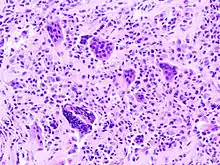

Micrograph of diffuse TGCT showing pigmented hemosiderin-laden macrophages (brown/red). H&E stain.

Diffuse TGCT is sometimes referred to as pigmented villonodular synovitis (PVNS), conventional PVNS, and D-TGCT.[1]:1[4]:361[6]:1[2]:102

Diffuse TGCT occurs less frequently and is locally aggressive (in some cases, tumors may infiltrate surrounding soft tissue).[3]:245[1]:1[2]:102[6][6]:1 It most commonly affects people under 40 years old, though the age of occurrence varies.[2]:102 Diffuse TGCT may occur inside a joint (intra-articular) or outside of a joint (extra-articular). Intra-articular tumors typically occur in the knee (approximately 75% of cases) and hip (approximately 15% of cases).[2]:102 Extra-articular tumors are usually found in the knee, thigh, and foot.[2]:101 Symptoms include swelling, pain, sensitivity, and/or limited range of motion.[2]:102 The rate of reoccurrence is estimated to be 18-46% for intra-articular tumors and 33-50% for extra-articular tumors.[2]:103[6]:1